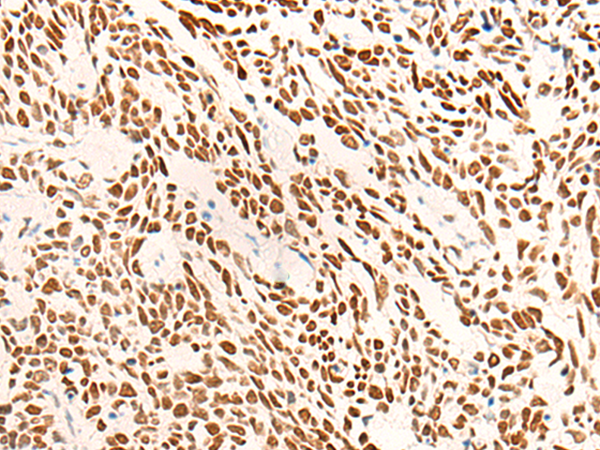

IHC positive control: |

Human colorectal cancer; |

IHC Recommend dilution: |

20-100 |